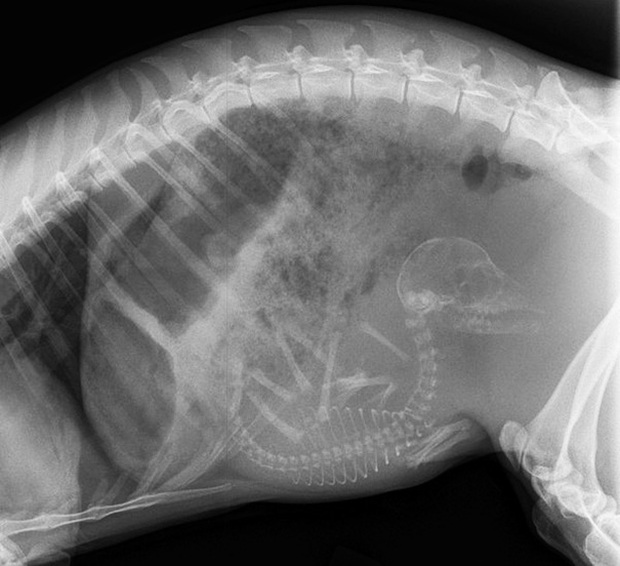

Một mẹ chim Kiwi đang mang trong mình quả trứng khá lớn so với kích thước bụng của nó. Chim Kiwi là loài chim không bay bản địa New Zealand. Trong họ nhà chim, trứng của Kiwi có kích thước lớn nhất khi so với kích thước cơ thể.

Cận cảnh hình chụp X-quang một cô mèo đang mang thai và loạt ảnh động vật mang bầu khiến người xem rùng mình nhưng rồi thấy đẹp khó tả - Ảnh 5.